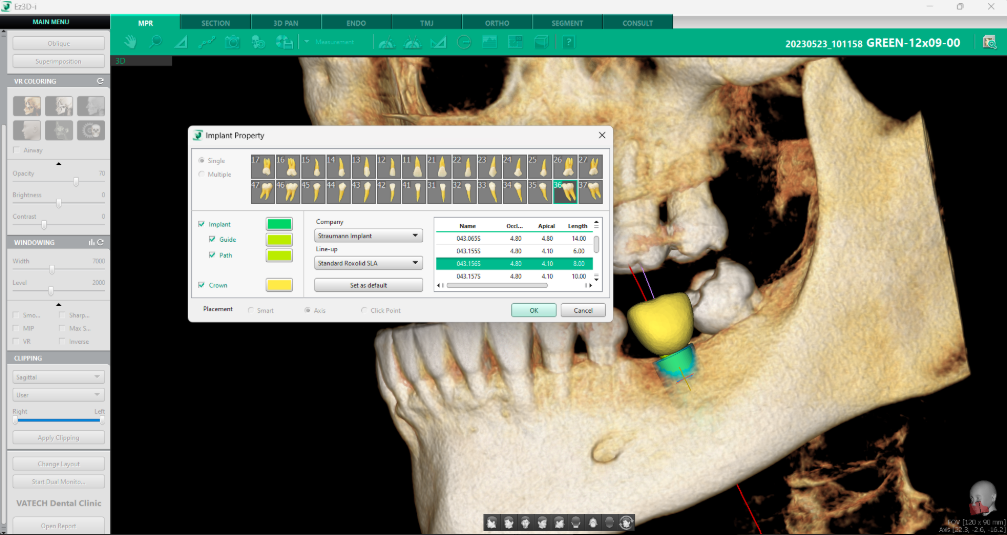

3. Tab-ul „Proprietăți Implant”

Unul dintre cele mai importante aspecte ale procesului de inserare a implanturilor este posibilitatea de personalizare și ajustare a fiecărui detaliu pentru a obține rezultate optime. Tab-ul „Proprietăți Implant” oferă o interfață intuitivă prin care pot modifica numeroși parametri ai implantului, asigurând o adaptare precisă la anatomia pacientului.

Accesarea acestui tab se face simplu, prin click dreapta pe implant și selectarea opțiunii ”Property”. Prima opțiune disponibilă în acest tab este alegerea între un implant unic sau plasarea mai multor implanturi simultan. Această funcționalitate simplifică procesul de restaurare dentară, permițând optimizarea distribuției implanturilor în funcție de necesitățile pacientului.

În plus, software-ul afișează clar dintele pe care urmează să fie inserat implantul, oferind posibilitatea de a modifica numărul dintelui în funcție de poziția acestuia. După confirmarea setărilor prin apăsarea butonului „OK”, modelul de coroană se va ajusta automat, reflectând noile specificații.

Din partea stângă a ferestrei, se pot activa sau dezactiva vizualizarea unor elemente esențiale, precum implantul, ghidul implantului, traiectoria acestuia și coroana dentară. Aceste opțiuni sunt complet personalizabile, inclusiv din punct de vedere al culorii, permițând o reprezentare vizuală clară și adaptată preferințelor utilizatorului.

În imediata apropiere a acestor opțiuni, software-ul permite selectarea producătorului și a liniei de implanturi preferate. Pentru a eficientiza procesul, se poate seta o variantă implicită, astfel încât AI-ul să recomande automat implanturile favorite la următoarele planificări.

Baza de date include informații actualizate despre toți producătorii importanți de implanturi, iar lista este periodic revizuită și completată prin colaborarea cu distribuitorii autorizați. În tabelul din dreaptă a ferestrei, software-ul afișează implanturile disponibile, corespunzătoare producătorului și liniei selectate, facilitând astfel alegerea optimă pentru fiecare pacient.